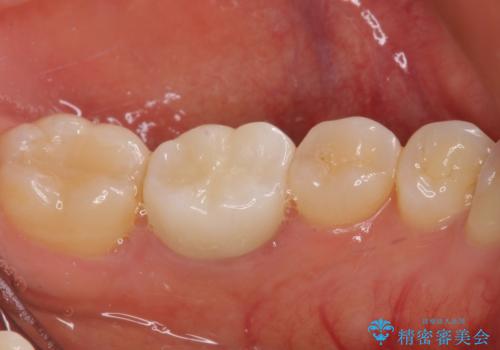

- 近医にてセラミックを装着した左下の奥歯に痛みが続いたとのことで来院された患者様です。

診査の結果、既に歯の神経は失活していたおり、排膿路が認められ、叩いたり触ったりしたときの痛みも確認されました。

根管治療を行った後にオールセラミッククラウンにて補綴することとしました。

初回の治療後には歯肉に認められた排膿の出口などの症状は消えていました。

補綴後6ヶ月経過しレントゲンを撮影したところ、遠心の歯根付近の病変が消失していることが確認できました。